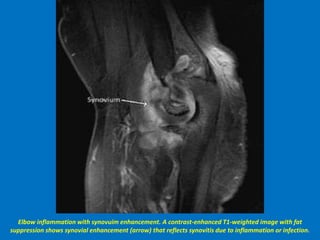

Elbow inflammation with synovuim enhancement. A contrast-enhanced T1-weighted image with fat

suppression shows synovial enhancement (arrow) that reflects synovitis due to inflammation or infection.